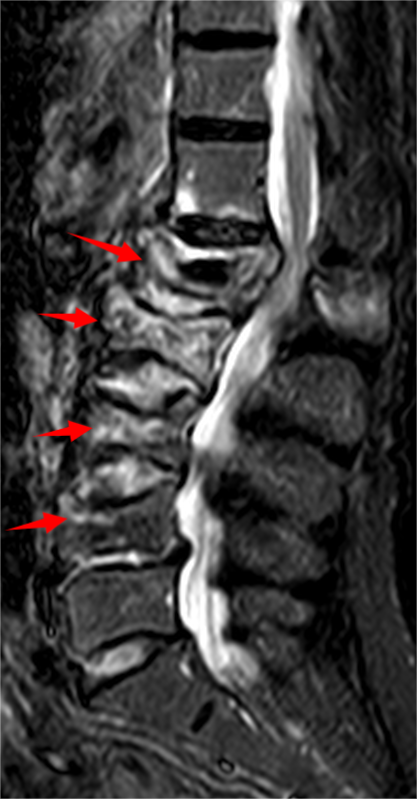

胸腰椎MRI检查结果显示:腰1椎体新近压缩性骨折伴积气,继发椎管狭窄;腰2、3椎体及腰4椎体上缘新近骨折。

影像学结果明确了患者为“骨质疏松伴多节段病理性骨折”,并伴有明显的脊柱后凸畸形和腰椎不稳。骨密度检测T值-4.25,提示重度骨质疏松。

影像学检查提示多节段脊柱病变

接诊后,科室为吴婆婆安排了详细的影像学检查,结果令人震惊。磁共振显示,她的骨折远非此前所知的一处,骨折下方的三节椎体腰2至腰4多个椎体都出现了新鲜压缩性骨折。更关键的是,最初的腰1椎体骨折并未愈合,属于“骨折不愈合”状态,并在重力作用下逐渐塌陷,导致脊柱后凸畸形(俗称“驼背”)。